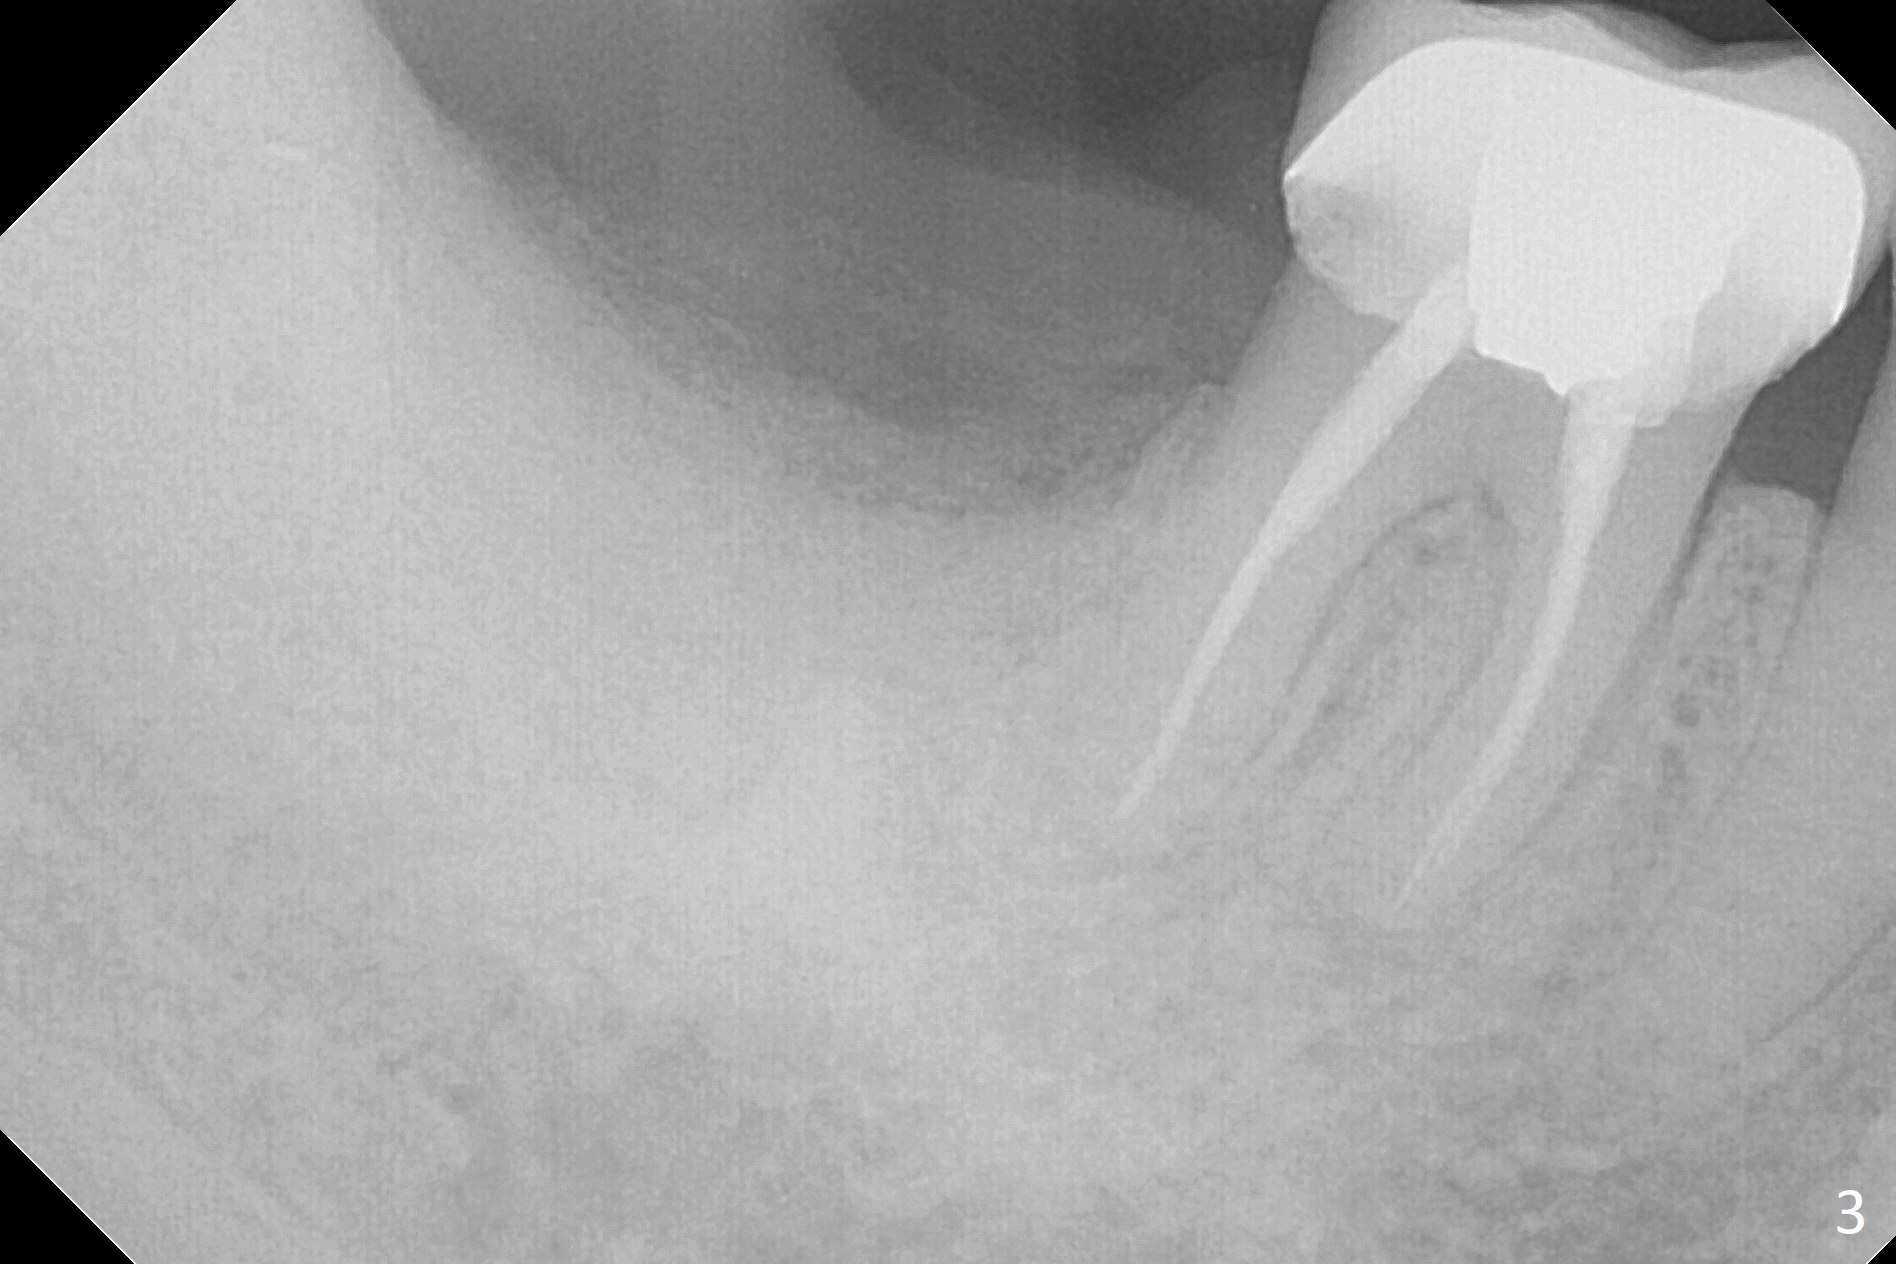

There is a mesiobuccal fistula at #31 with periimplantitis (Fig.1 ^). The bone loss is severe before and after implant removal (Fig.2). It is impossible to place bone-level implant in the original osteotomy due to insufficient bone height. There is pain when a new osteotomy is being initiated in the mesial slope. Following placement of Vera Graft (Fig.3), collagen plug and 6-month resorbable membrane, the wound is closed with suture (mild tension). Postop, there is oozing. Periodontal dressing should have been applied. If the ridge can be preserved in 4-6 months, a 11 mm long implant (Fig.4 green line with 4 mm of the native bone) can be placed with 1.9 mm clearance (red dashed line: the superior border of the Inferior Alveolar Canal); the abutment is estimated to have 4 mm cuff (pink). The socket appears to be healing 8 days postop (Fig.5). The ridge remains wide 5 months post implant removal, although the bone density is low (Fig.6,7 (still ~ 1000 units). It seems that a 5x11.5 mm implant could be placed in the mesiobuccal aspect of the bony defect (Fig.8). For better occlusion, the implant should be shorter (5x8.5 mm) after discussion with the guide lab (Fig.9). Make sure that the most coronal thread is buried by the bone graft, i.e., underneath the crest(>).